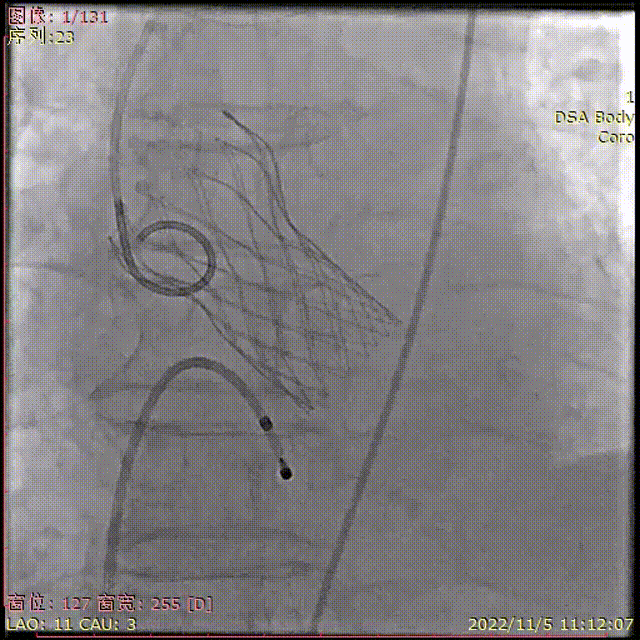

术中影像

主动脉根部造影

导丝顺利跨瓣

TaurusElite输送器顺利过弓

瓣膜初始定位

瓣膜稳定释放到工作位,无位移

工作位多角度评估

瓣膜完全释放